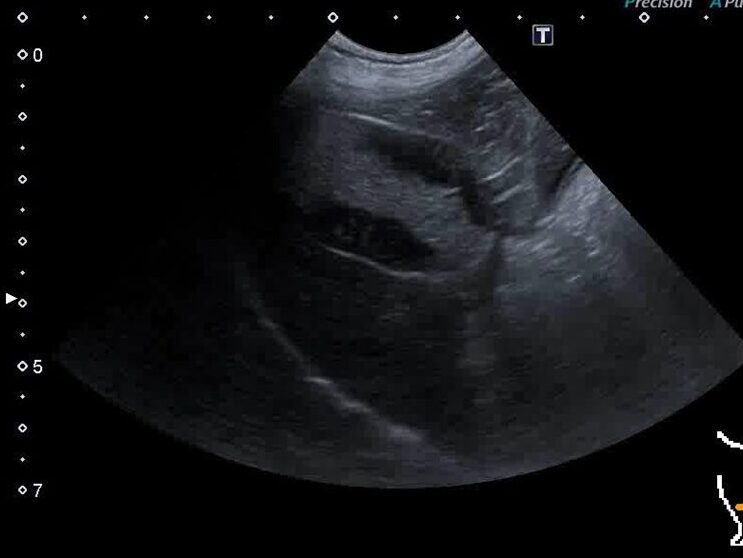

超音波検査で典型的な胆嚢粘液嚢腫が見つかりました。幸いにも、まだ症状はありませんでした。

胆嚢粘液嚢腫のエコー画像